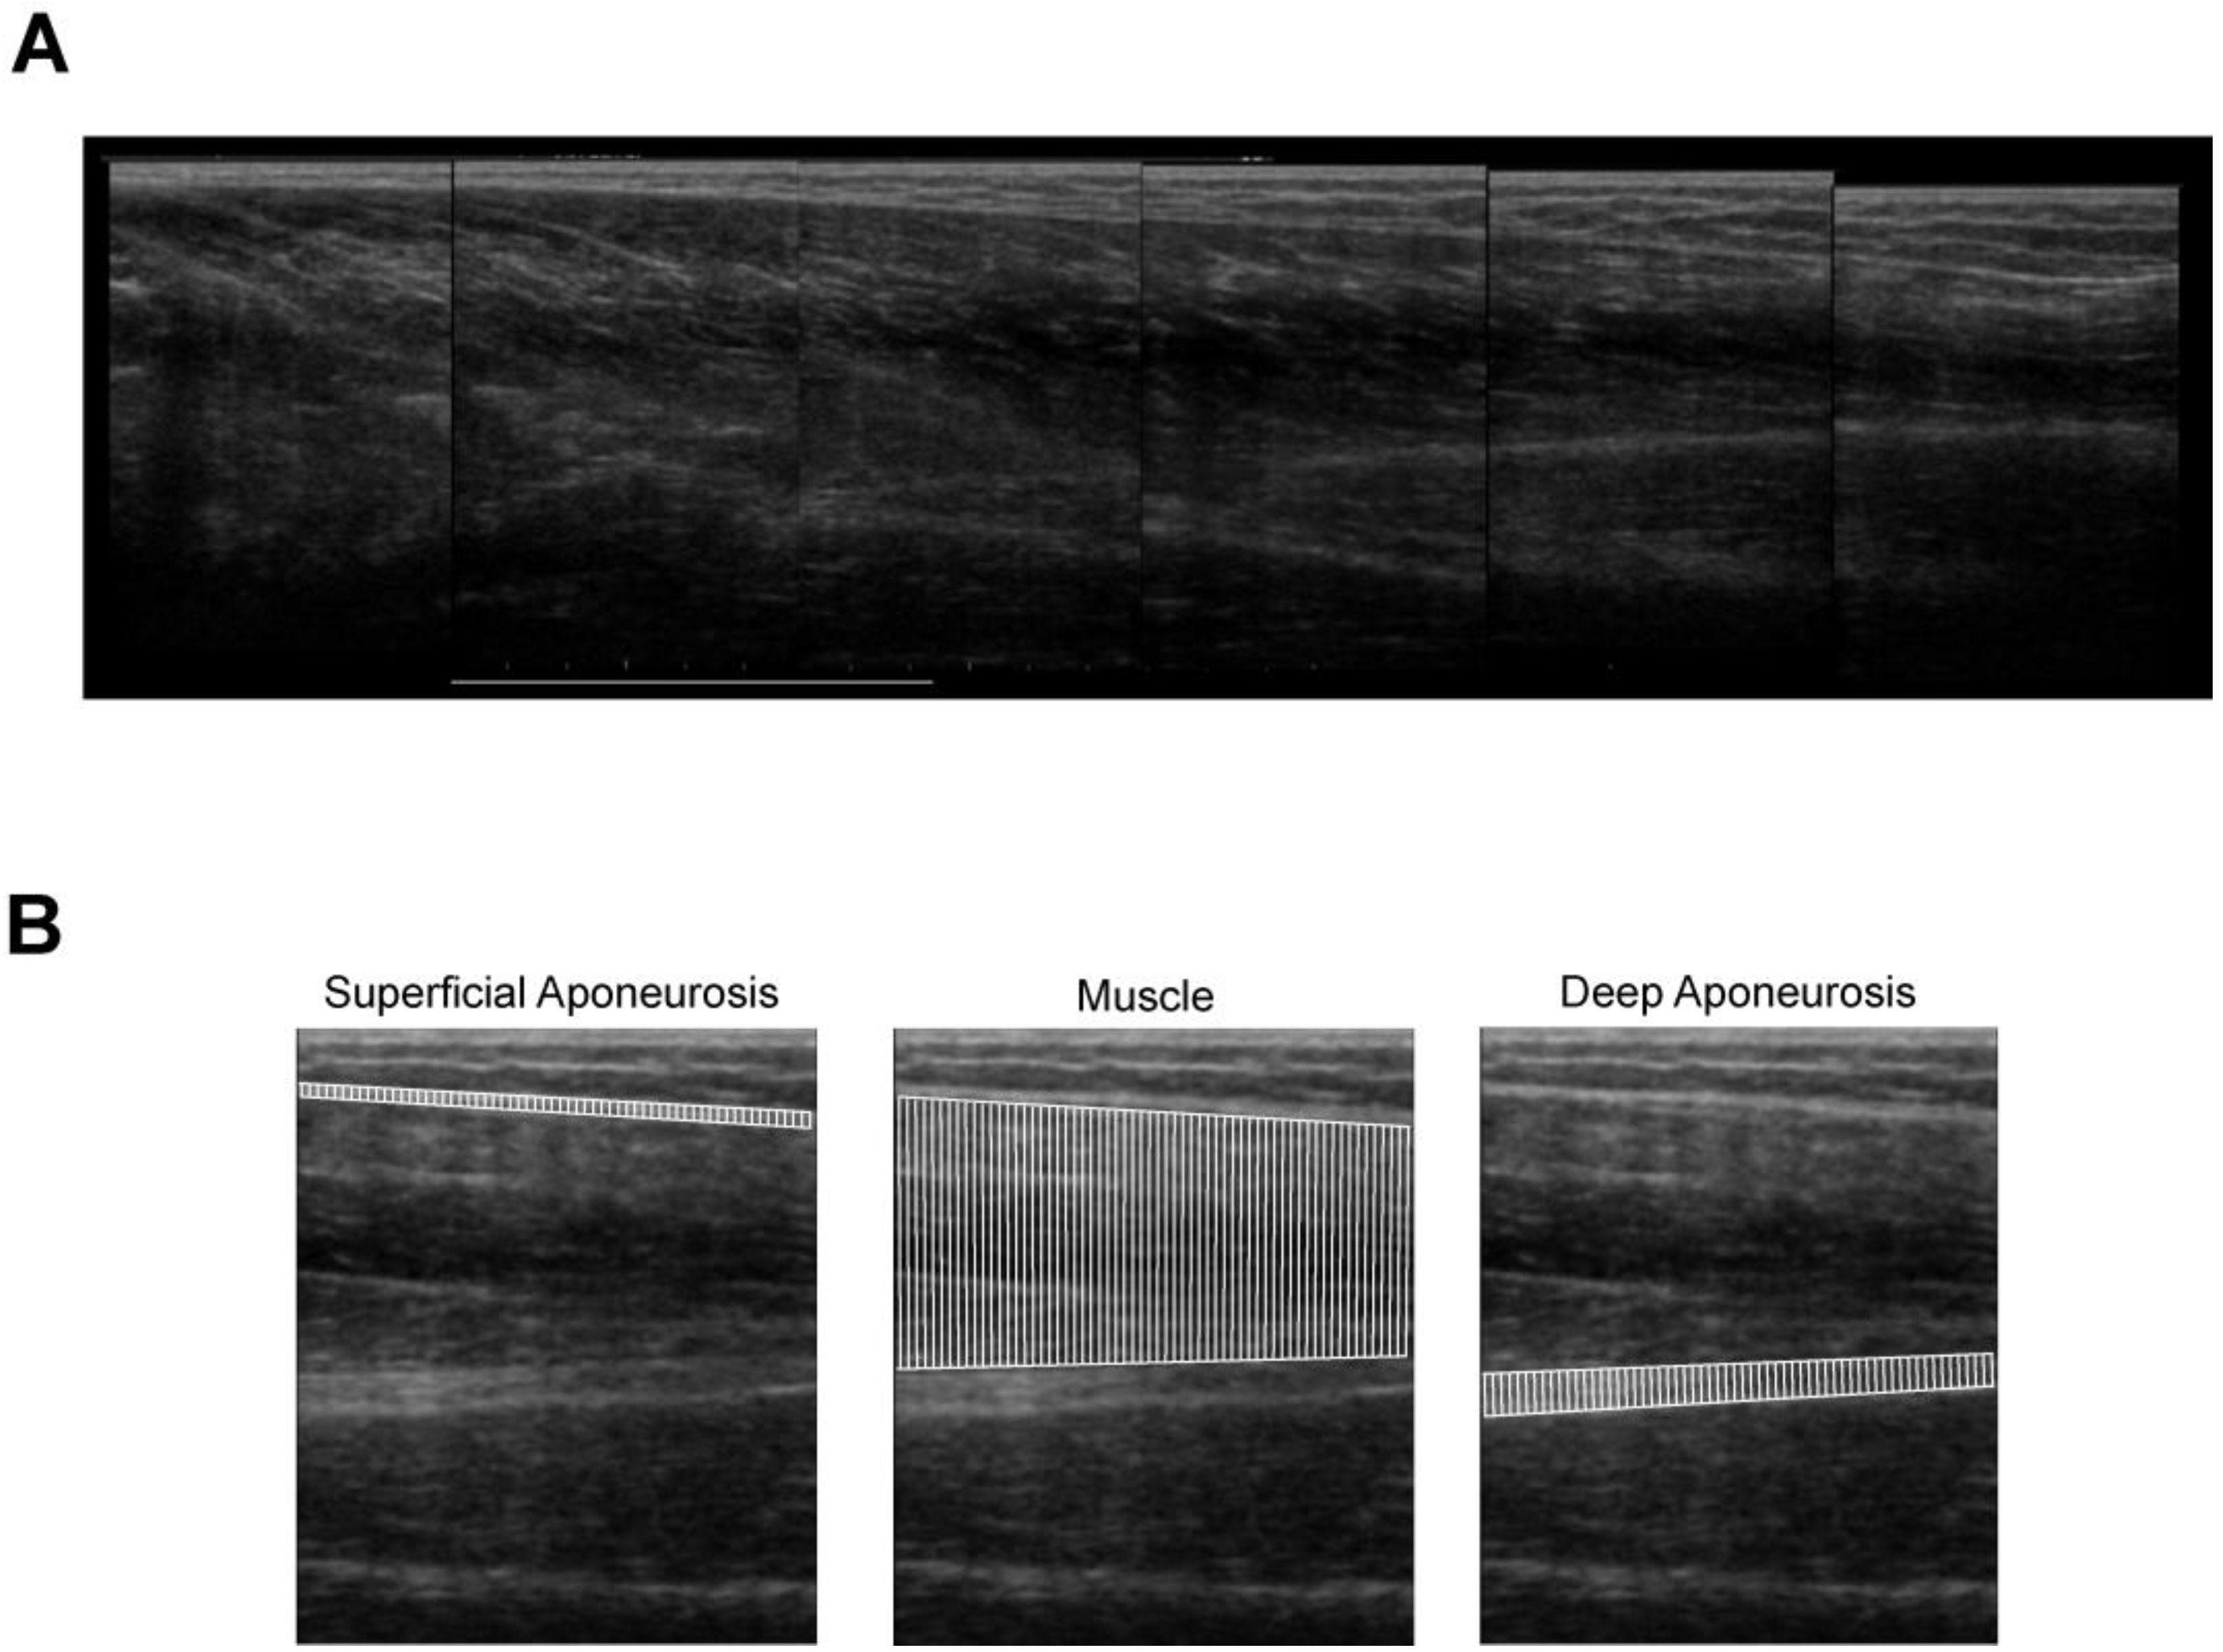

2.4. Image Analysis